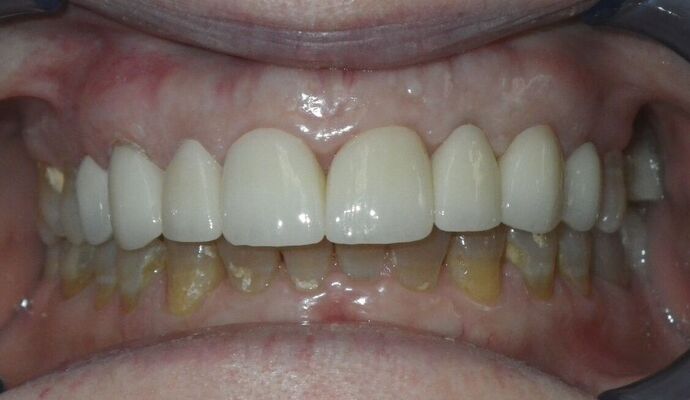

Cosmetic Changes with Veneers and Crown and Bridge: Case 1

Patient presented with spacing between upper central incisors and dark tetracycline stains that she wanted corrected